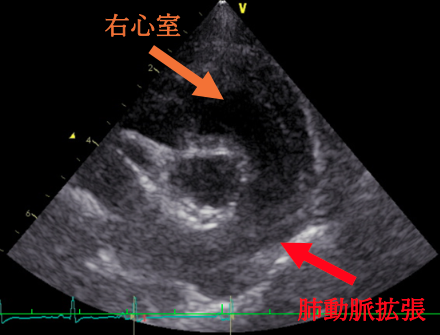

今回の⼼臓超⾳波検査では、 三尖弁からの⾎液の逆流が以前よりも増えていることが確認されました。 また、右⼼室の圧⼒が⾼くなり、左⼼室が押されて細く⾒えるような所⾒や、肺動脈の拡張も認められました。現在、⽇常⽣活で症状はありませんが、⼼臓への負担が以前より増えている状態のため、肺の⾎管を広げて⼼臓の負担を軽減するお薬の内服を始めることになりました。

肺⾼⾎圧症とは、肺に⾎液を送る「肺動脈」の⾎圧が上がる状態を指します。